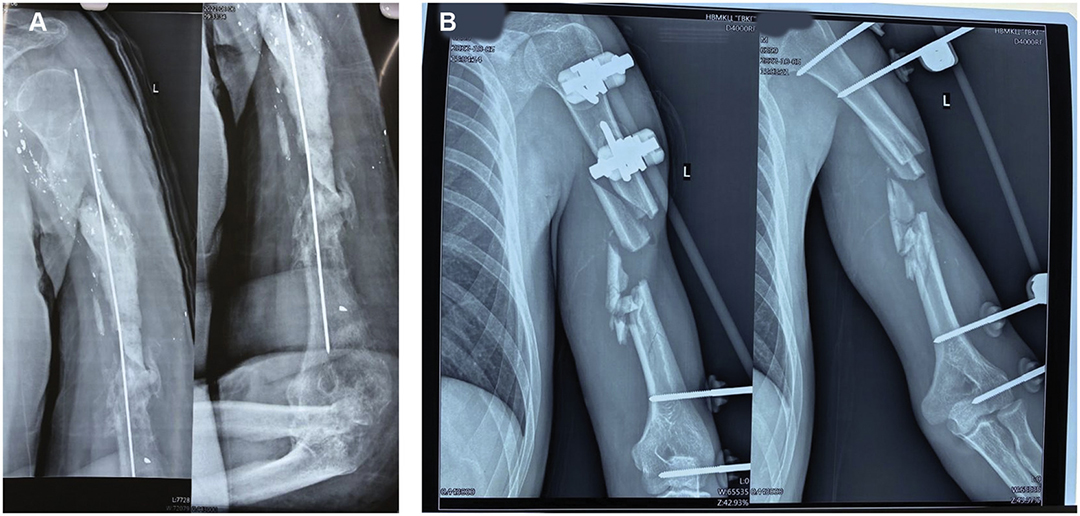

依据 2018 年修订版的 AO/OTA 骨折与脱位分类标准,4 例(占 17%)患者属于单纯性 A 型骨折,8 例(占 33%)为 B 型骨折,12 例(占 50%)为多片段及节段性 C 型骨折。肱骨的多片段严重骨折情况可参考图 1 和图 2。

图 2.左肱骨枪伤骨折的 X 射线胶片。左肱骨骨干枪击多碎裂患者,存在骨缺损和碎片移位。B.左肱骨骨干中三分之一处枪伤粉碎性骨折,伴有骨缺损和碎片移位。